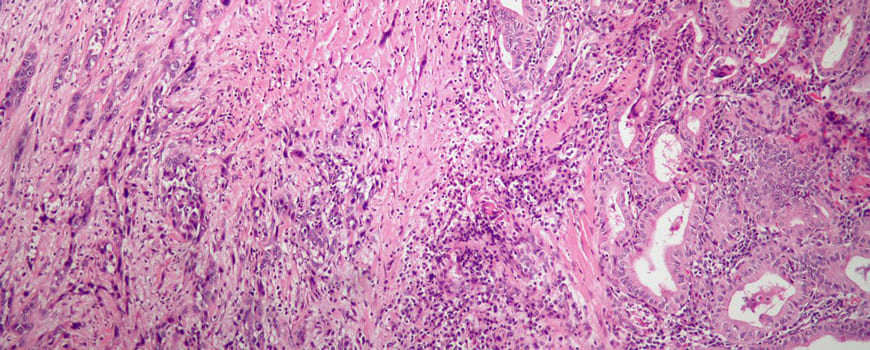

Haşimoto tireoiditi (xronik tireoidit) immun sistemin öz sağlam qalxanvari vəzi hüceyrələrini (bu hüceyrələr "tireositlər" adlandırılır) "yad" hüceyrələr kimi qəbul edərək onları məhv etməsi nəticəsində yaranan autoimmun xəstəlikdir. Nəticədə, tiroid vəzi tədricən məhv edilir və bəzən tiroid hormonlarının səviyyələri qeyri-kafi olur. Xəstəlik ilərdikçə vəz daha az hormon istehsal edərək hipotiroidizm inkişaf edə bilər. Bəzi hallarda normalda kafi olan hormon səviyyəsi hamiləlik dövründə çoxalan hormon ehtiyacınl qarşılamaya bilər və bu zaman hamiləlik və süd vermə dövründə dərman dəstəyi almaq tələb oluna bilər. Sonra dərman kəsilib vəzin funksiyasını yetərli mi deyə yoxlanılır.